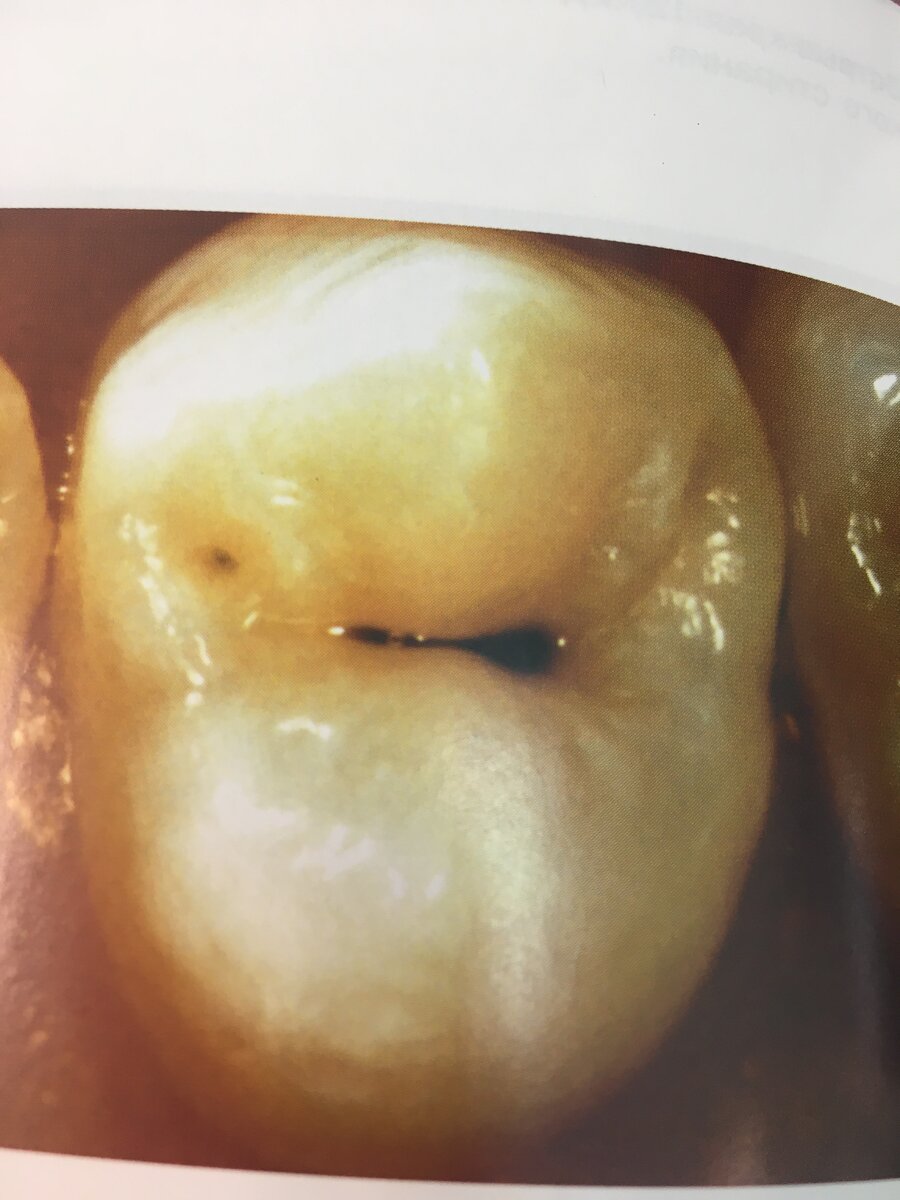

В настоящее время ни у кого не возникает сомнения, что кариозный процесс начинается с деминерализаци (уменьшение минералов) Факторы, влияющие на возникновения кариеса зуба, принято делить на общие и местные. Кариесрезистентность. Интенсивность поражения зубов кариесом в различных регионах нашей страны колеблется в широких пределах . Важная роль в повышении устойчивости к кариесу принадлежит фтору, который обуславливает устойчивость эмали. В формировании и поддержании резистентность к кариесу значительна роль принадлежит ротовой жидкости. Она обладает минерализирующей способностью за счёт содержания в ней тонов кальция, фосфора и фтора. Факторы влияющие на развитие кариеса: 1.Питание( чем больше углеводов, тем больше риск) 2.Перенесенные заболевания( туберкулёз, ревматизм) 3. Роль микроорганизмов. 4.Зубная бляшка- это скопление бактерий, которые плотно фиксированны на поверхности зуба. P.s. Посещайте врача-стоматолога 2 раза в год.

В настоящее время ни у кого не возникает сомнения, что кариозный процесс начинается с деминерализаци (уменьшение минералов)

4.Зубная бляшка- это скопление бактерий, которые плотно фиксированны на поверхности зуба.